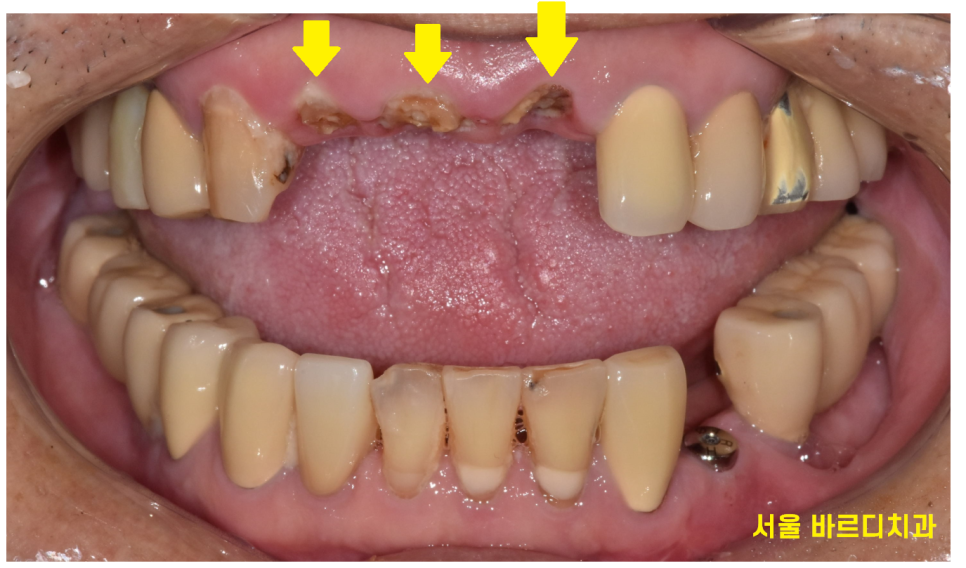

앞니 3개가 완전히 부러졌습니다.

사고 발생입니다.

3개의 부러진 앞니

기존에 신경치료 후 기둥까지 보강하여

씌운 치아였는데요.

가뜩이나 약한 치아인데 넘어지면서

치아에 충격이 제대로 갔네요ㅠㅠ

다른 치아, 입술에 문제가 없는지 1차적으로 확인

아래 앞니도 살짝 깨져있네요~

이건 큰 문제가 아니고